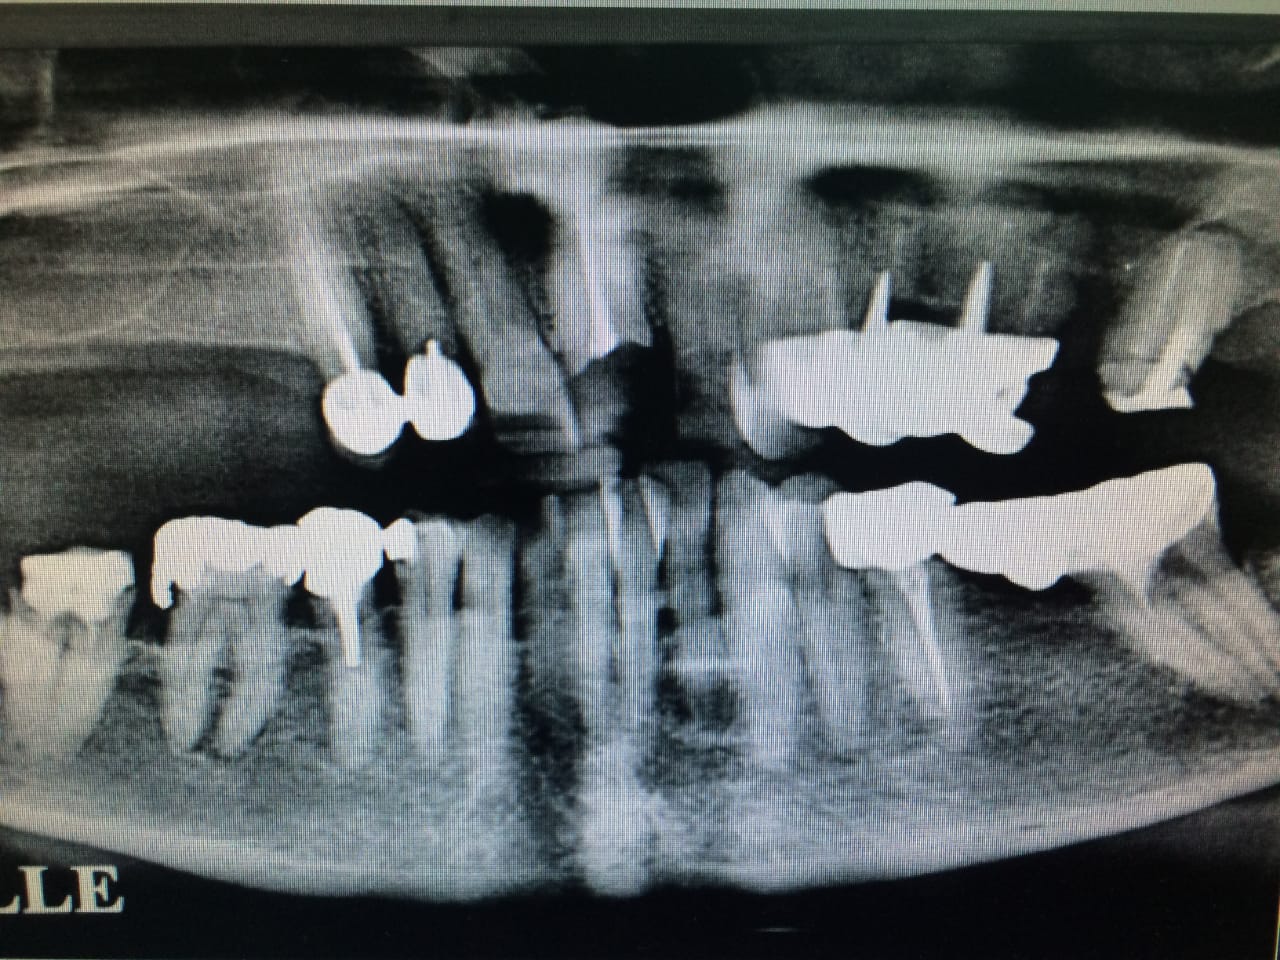

→ Avant l’intervention

Après une étude approfondie de vos antécédents dentaires et médicaux, le dentiste détermine si les implants dentaires sont indiqués dans votre cas. Il examine ce qui doit être fait, se prépare et vous explique en plan de traitement à venir.

→ Pose du ou des implants

Durant cette étape, le praticien pose les implants dentaires pour remplacer les racines manquantes. À l’issue de cette intervention, vous sentirez des implants couverts par la gencive, et qu’ils sont mis en “nourrice” : cela permet à l’os de cicatriser autour des implants.